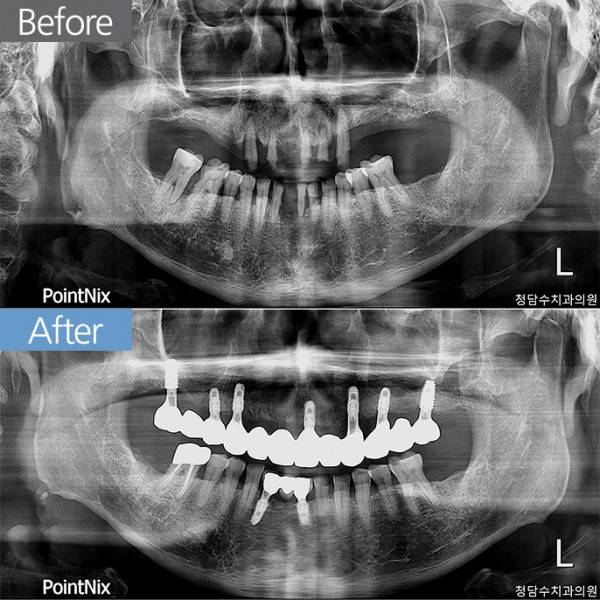

임플란트 60대남 임플란트

60대남 임플란트